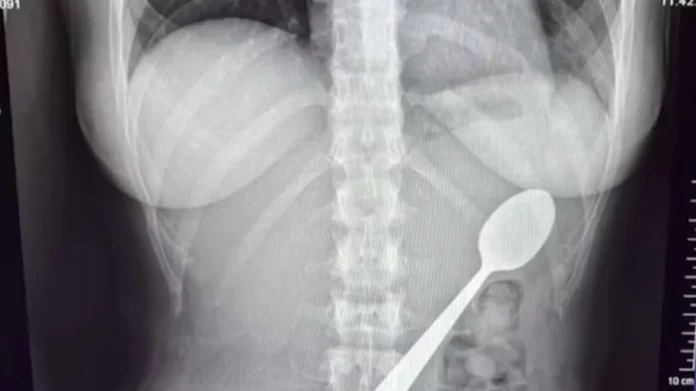

Μια 28χρονη στο Βέλγιο κατάπιε κουτάλι 17 εκατοστών όταν πήδηξε πάνω της ο σκύλος της

Η νεαρή περίμενε να έρθει στο σπίτι ένας φίλος της, με τον οποίο μάλιστα έφαγαν δείπνο, ενώ ο κουτάλι ακόμα βρισκόταν στον οισοφάγο της